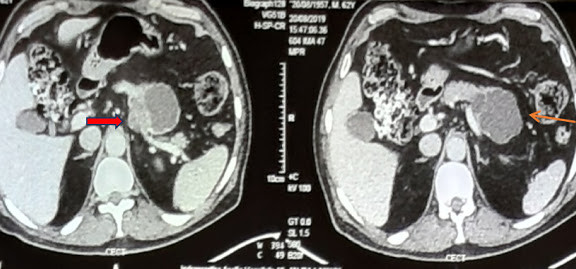

A 62 yearold gentleman presented to us with complaints of upper abdominal pain with radiation to back since 2 months. He also complained of weight loss, […]